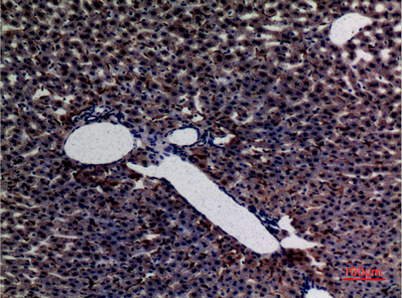

Product name: Amylase rabbit pAb

Dilutions: Western Blot: 1/500 - 1/2000. IHC-p: 1:100-300 ELISA: 1/20000. Not yet tested in other applications.

Immunogen: The antiserum was produced against synthesized peptide derived from the N-terminal region of human AMY1/2. AA range:61-110